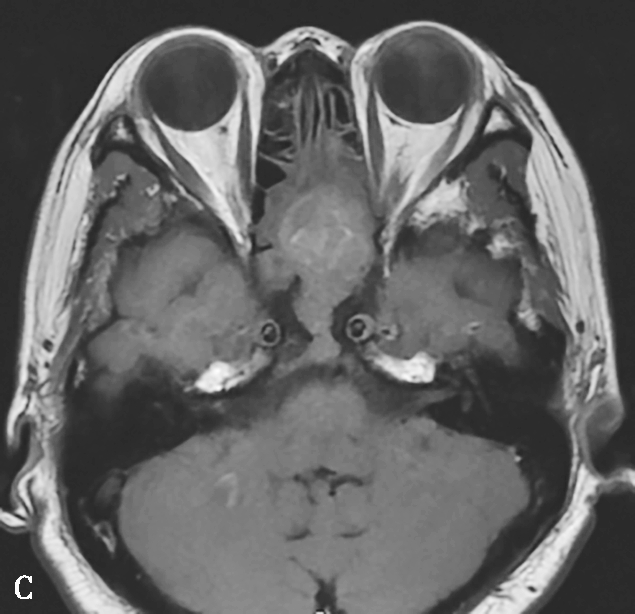

图1-3-23 急性侵袭性真菌性鼻窦炎

A、B.横断面、冠状面CT骨窗,示双侧蝶窦、后组筛窦软组织影,密度不均,窦壁骨质硬化伴局部骨质破坏,累及双侧圆孔、翼管;C~E.MRI横断面T 1 WI、T 2 WI、T 1 WI+FS+C,示双侧蝶窦、后组筛窦内混杂长T 1 、长T 2 信号,窦腔内见斑片状短T 1 、短T 2 信号影,增强扫描边缘强化,前颅底脑膜增厚强化